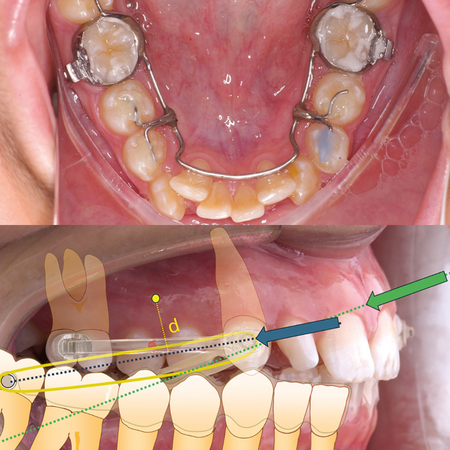

Variações na aplicação da força no distalizador tipo Carriere. Parte II: efeito nos molares inferiores

INTRODUÇÃO: Essa Parte II discute sobre a diagramação mecânica de distalizadores tipo Carriere. OBJETIVO: O objetivo é analisar o impacto dessa diagramação no plano vertical/anteroposterior da dentição inferior. CONCLUSÃO: Foi realizada uma análise do posicionamento dos acessórios de apoio, sugerindo que a aplicação da força no primeiro molar, deslocada para mesial, reduz a tendência a angulações indesejadas, minimizando os efeitos colaterais.

Variations in the application of force in  the Carriere type distalizer. Part II:  Effect on lower molars

INTRODUCTION: This Part II discuss the mechanical diagramming of Carriere type distalizers. OBJECTIVE: The objective is to analyze the impact of this diagramming in the vertical/anteroposterior plane of the mandibular dentition. CONCLUSION: An analysis focusing on the positioning of supporting accessories was performed, suggesting that applying force to the first molar, positioned more mesially, reduces the tendency for unwanted angulation, minimizing side effects.